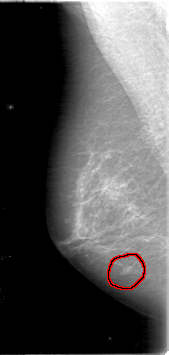

D_4011_1.RIGHT_MLO

FILE: D_4011_1.RIGHT_MLO.OVERLAY

TOTAL_ABNORMALITIES 1

ABNORMALITY 1

LESION_TYPE MASS SHAPE OVAL MARGINS OBSCURED

ASSESSMENT 0

SUBTLETY 4

PATHOLOGY BENIGN

TOTAL_OUTLINES 1

BOUNDARY